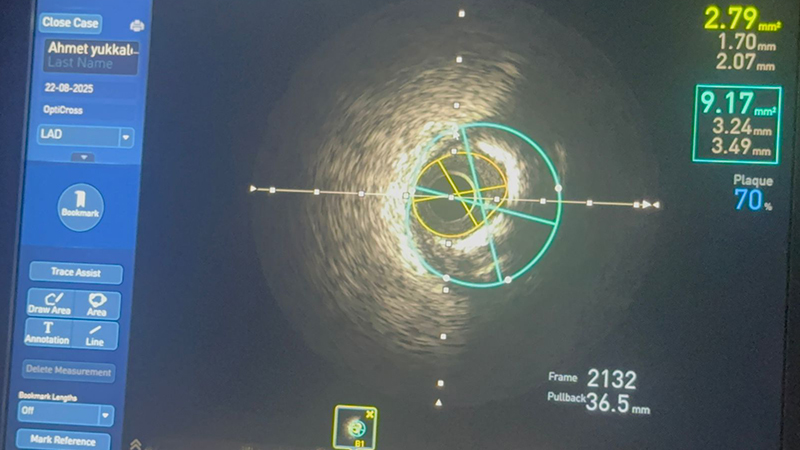

İşlem sırasında kullanılan IVUS yöntemi sayesinde, damar yapısı ve darlığın derecesi yüksek çözünürlüklü görüntülerle incelendi.

İleri teknoloji yöntemlerden biri olan intravasküler ultrason (IVUS), damarların iç yüzeyini ayrıntılı biçimde görüntüleme imkânı sunuyor.

Özellikle stent yerleştirilmesi gereken vakalarda işlem başarısını artıran IVUS, aynı zamanda komplikasyon riskini de azaltıyor.